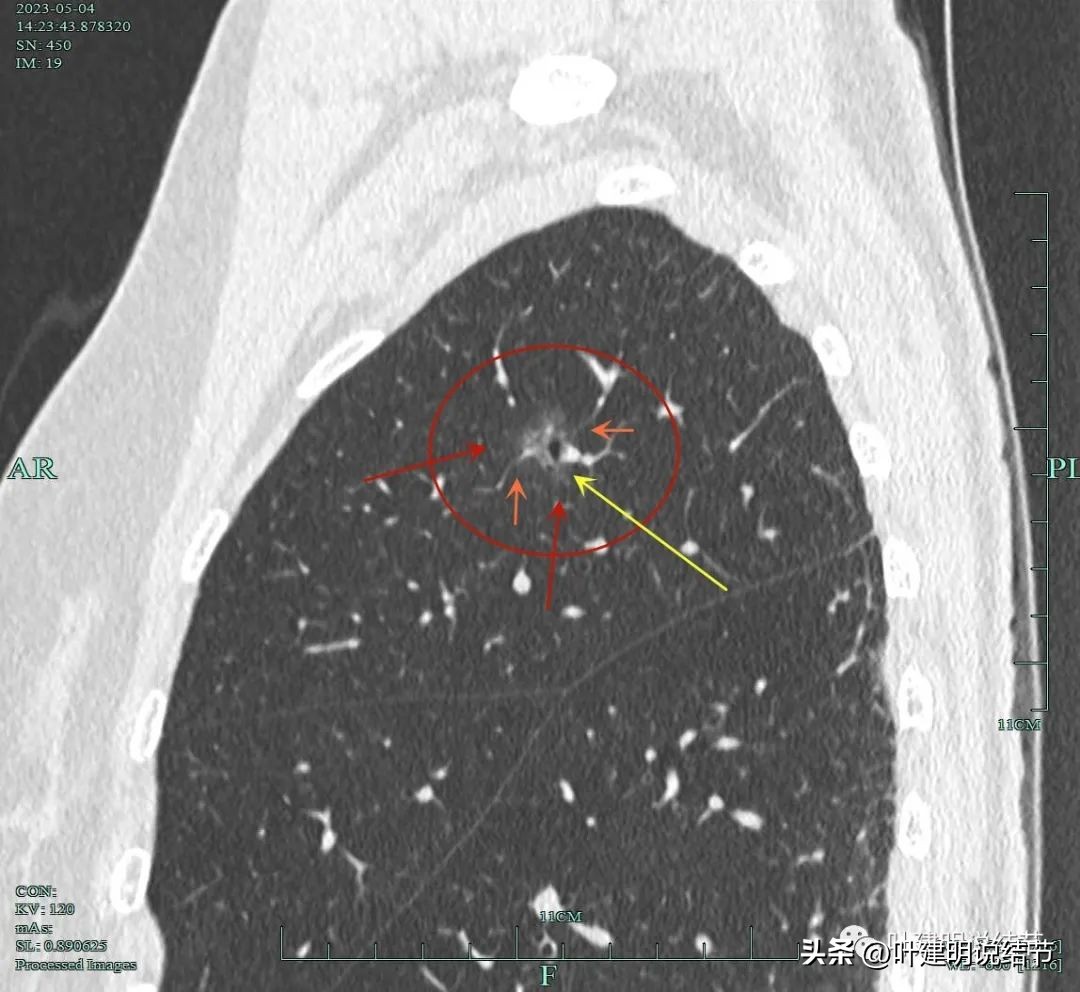

靶扫描重建发现病灶内部穿行血管毛糙,细支气管扩张,边缘毛刺样征。

灶内走行的血管模糊、异常增粗与毛糙。病灶总体轮廓较清,磨玻璃部分密度较低。

上图显示明显的血管弯征。而且磨玻璃病灶密度欠均匀。

病灶分叶、细支气管扩张,微小血管进入;整体轮廓较清。

上图这个视角清楚显示灶内的空泡征是扩张的细支气管。而且灶外细些,灶内更远离肺门,反而扩张,说明病灶有牵拉力呀!

边缘有毛刺征,灶内密度欠均。